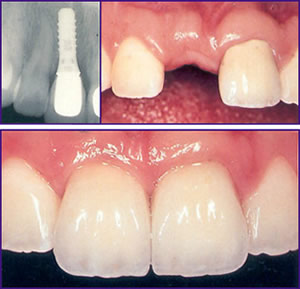

Implant Of Front Tooth